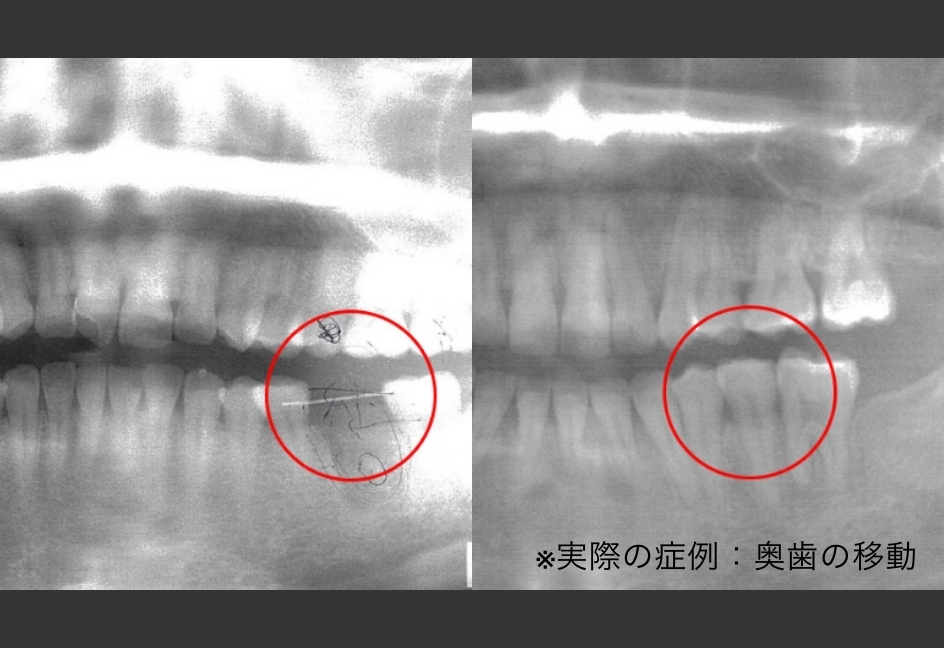

従来の矯正治療では、スペース不足の場合に健康な歯を抜歯することが一般的でした。しかし3D-LSTでは、歯体移動技術により大臼歯の近心移動が可能となり、第一大臼歯の抜歯を回避できるケースが大幅に増加しました。

また、従来の傾斜移動では対応が困難だった症例や、他院で「治療不可能」とされた難症例にも対応可能。患者様の貴重な歯を守りながら、理想的な歯列と機能を実現する新しい治療選択肢を提供しています。